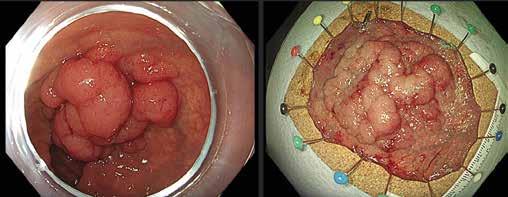

Små konkrementer i pankreas hovedgang (< 5 mm) kan ofte fjernes endoskopisk ved at strikturer dilateres og konkrementet hentes

ut med konvensjonelle metoder (Fig 4). Større konkrementer er mer krevende og kan behandles med ESWL eller pankreatikoskopi og fragmentering av konkrement(ene) med sjokkbølgelitotripsi eller laser. Selv om man tilsynelatende klarer å fjerne alle konkrementer fra hovedgangen er tilbakefallsfrekvensen høy og pasientene risikerer langvarig stentbehandling (vanligvis en eller flere plaststenter) og gjentatte endoskopiske prosedyrer.